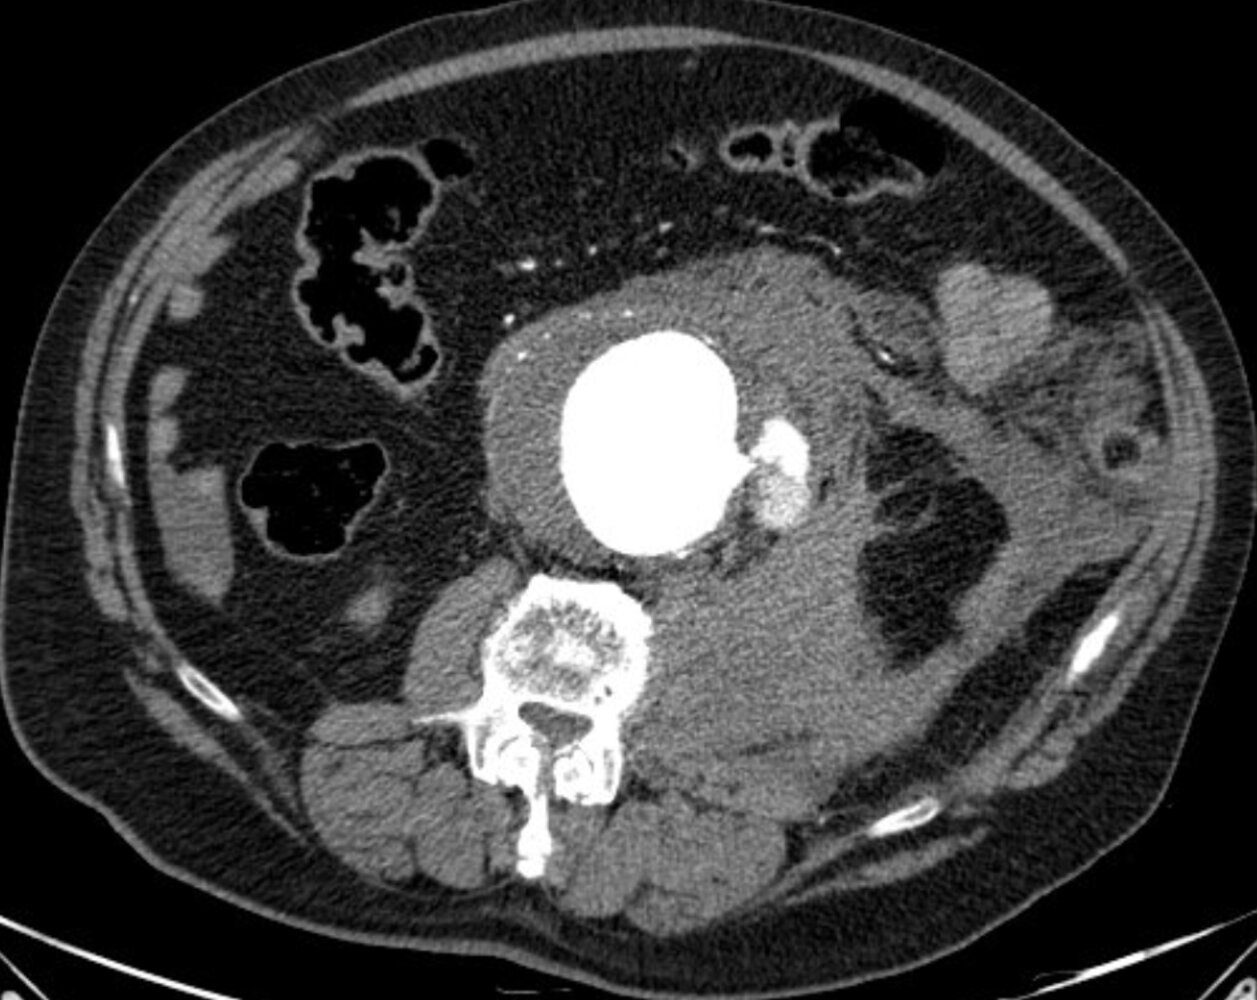

CTA thorax, abdomen, and pelvis

-

Study of choice if imaging can be performed without delaying operative repair [12][17]

- Higher detection rates for contained rupture and retroperitoneal bleeds than ultrasound

- Allows surgeons to determine if a patient is suitable for EVAR

- Characteristic findings

- Sign of impending rupture: high-attenuation crescent within mural thrombus [18]

- Signs of rupture: retroperitoneal hematoma, retroperitoneal stranding, indistinct aortic wall, extravasation of contrast

![]()